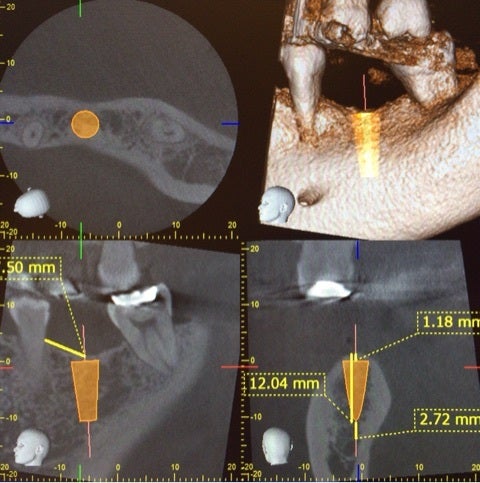

それでは当院でのインプラント手術の例です。

患者様は左下の奥歯が欠損してしまい、しっかり食事を摂りたいという希望で無痛治療でのインプラント手術を選択されました。

術前に綿密にシミュレーションを行っていたものとほぼ同じ位置に埋入されていることが確認できます。

今回は術後の痛みや腫れが殆ど無かったとのことで患者様には大変喜んで頂き、歯が入ることを楽しみにされています。

今後はこの歯茎から見えるインプラントに歯の形を作成していきます。

今回は埋入手術の話ですが、当院では上記にお話ししたインプラントの成立要件を全て確認し、シミュレーションを行い手術を行っています。